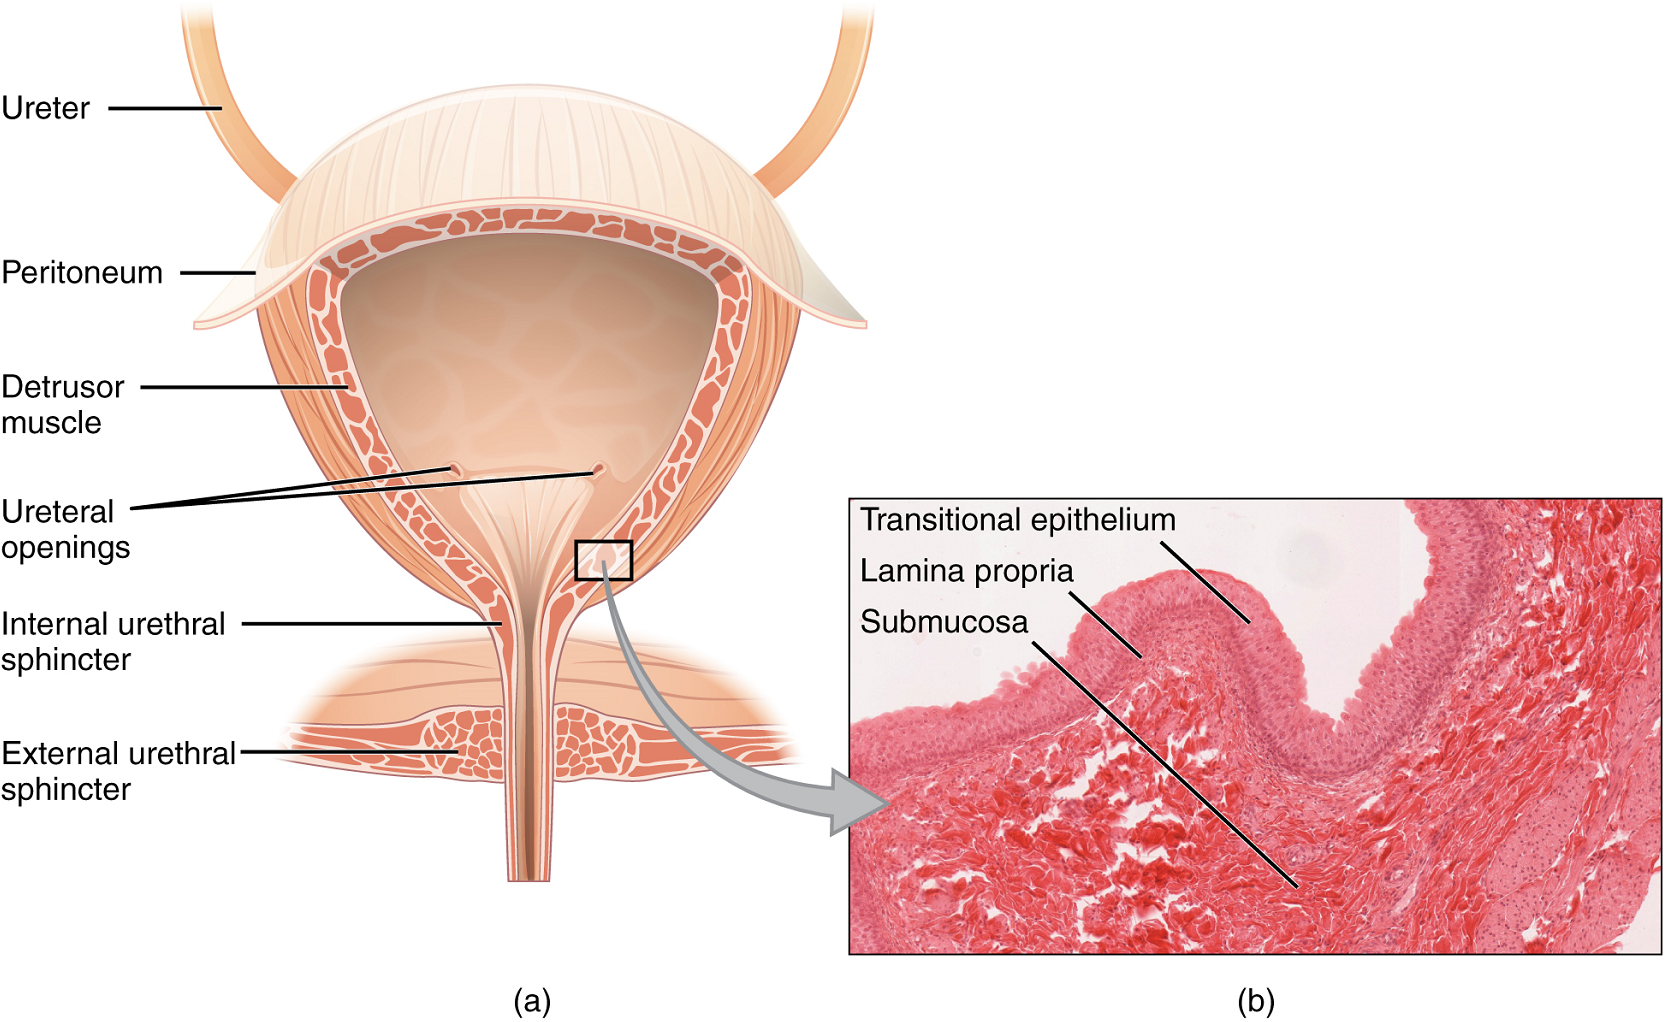

Bladder

The urinary bladder collects urine from both ureters (Figure 5). The bladder lies anterior to the uterus in females, posterior to the pubic bone and anterior to the rectum. In males, the anatomy is similar, minus the uterus, and with the addition of the prostate inferior to the bladder. The bladder is partially retroperitoneal (outside the peritoneal cavity).

The bladder is a highly distensible organ comprised of irregular crisscrossing bands of smooth muscle collectively called the detrusor muscle. The interior surface is made of transitional epithelium that is structurally suited for the large volume fluctuations of the bladder. Volumes in adults can range from nearly zero to 500–600 mL.

The detrusor muscle contracts with significant force in the young. The bladder’s strength diminishes with age, but voluntary contractions of abdominal skeletal muscles can increase intra-abdominal pressure to promote more forceful bladder emptying.

Urethra

The urethra transports urine from the bladder to the outside of the body for disposal. The urethra shows significant anatomic difference between males and females; all other urine transport structures are identical (Figure 6).

The urethra in both males and females begins inferior and central to the two ureteral openings. (Figure 5a). In both males and females, the proximal urethra is lined by transitional (stratified epithelium which can contract and expand) epithelium, whereas the terminal portion is a nonkeratinized, stratified squamous epithelium. Voiding is regulated by an involuntary autonomic nervous system-controlled internal urinary sphincter, consisting of smooth muscle and voluntary skeletal muscle that forms the external urinary sphincter below it.

The ureters are approximately 30 cm long. The inner mucosa is lined with transitional epithelium (Figure 5) and scattered goblet cells that secrete protective mucus. The muscular layer of the ureter consists of longitudinal and circular smooth muscles that create the peristaltic contractions to move the urine into the bladder without the aid of gravity (Figure 4).